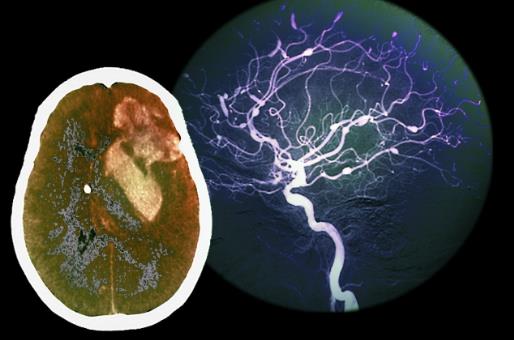

大腦:20歲開始衰老

隨著我們年齡越來越大,大腦中神經細胞(神經元)的數量逐步減少。我們降臨人世時神經細胞的數量達到1000億個左右,但從20歲起開始逐年下降。到了40歲,神經細胞的數量開始以每天1萬個的速度遞減。